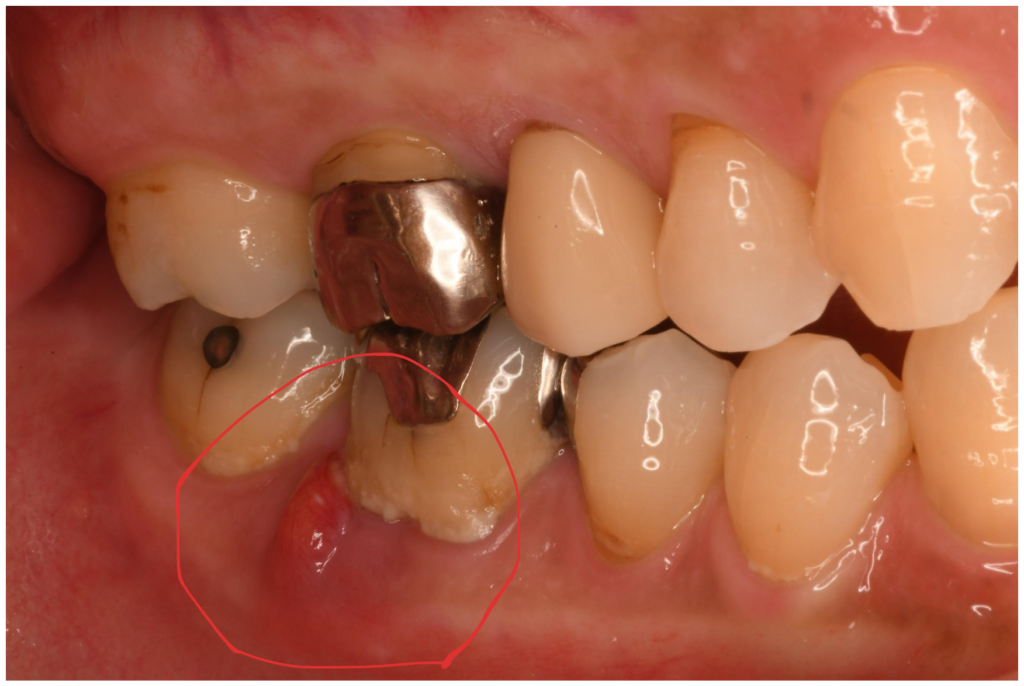

右下6番の痛み・歯ぐきの腫れで来院された方の治療(根管治療)【保険診療】

「右下の奥歯が痛い」「歯ぐきが腫れている」という症状でご来院された患者さんの治療内容をご紹介します。 初診時、右…